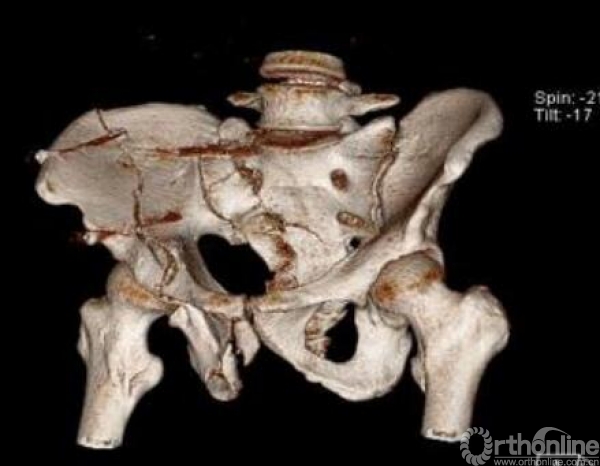

术前骨盆CT三维重建(2017.09.17)

术前骶尾椎CT三维重建(2017.09.17)